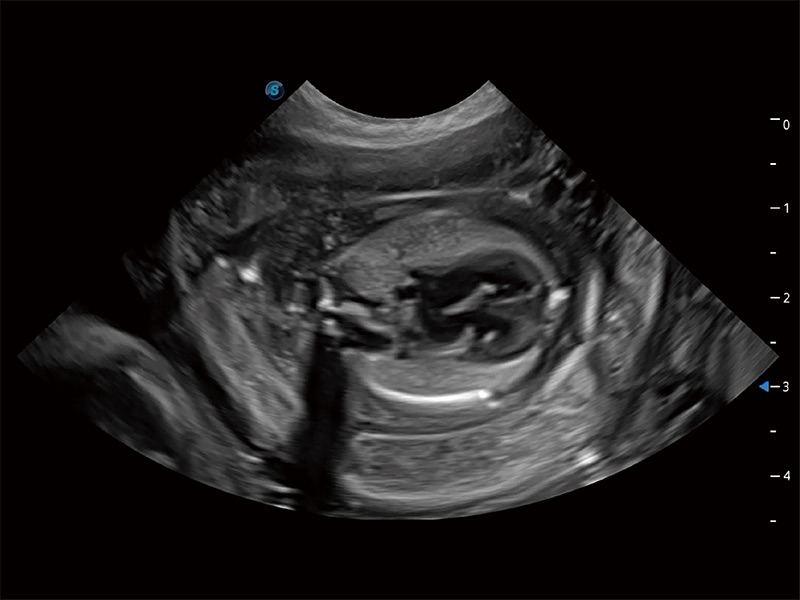

ProPet 80 專為動物醫(yī)生設(shè)計,對不同的動物體型和生理結(jié)構(gòu)作出了針對性的優(yōu)化。通過動物影像專用軟件,可滿足個性化的應(yīng)用需求,幫助動物醫(yī)生獲得更精確的診斷數(shù)據(jù)。

ProPet 80 全新的動物超聲智能軟件和豐富的探頭群,為動物醫(yī)生提供了高清晰度和精細(xì)分辨率的圖像,無論在寵物、馬科、畜牧還是實(shí)驗(yàn)室動物等應(yīng)用中都可以輕松應(yīng)對,為您的日常工作帶來滿意的體驗(yàn)。